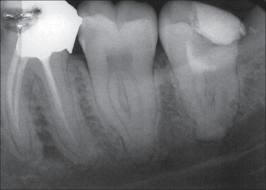

Rx de molares inferiores mostrando la disposición de las raíces y sus conductos.

1º Molar inferior: El orificio de entrada del conducto distal se encuentra ensanchado en sentido buco lingual, debe sospechar la existencia de un cuarto conducto.

La localización  de un cuarto conducto se lleva a cabo con la técnica radiológica de Clark o por medio de una lima curvada en distal para sondear la pared lingual ó vestibular del conducto distal. Imagen inferior